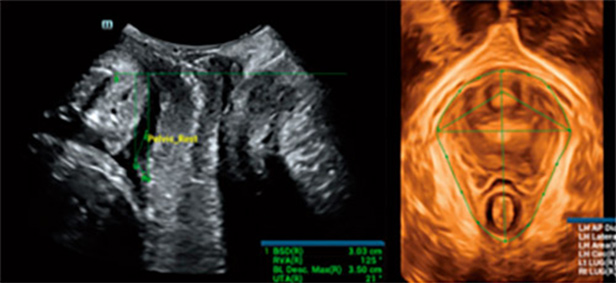

为了帮助医生在复杂的盆底检查中快速获得标准切面及测值,提高诊断效率,仁合针对此应用场景提出了智能盆底超声解决方案Smart Pelvic,它能够自动获取全盆腔测量指标,自动成像及获取肛提肌裂孔三维成像、前后径、左右径、面积以及尿道肛提肌间隙七个测量指标。医生只需通过极其简单的几步交互就可以获得准确评估所需要的临床数据,其操作时间仅有传统操作的 1/3。同时,仁合提供业界主流的三大标准体系供选择使用,支持不同类型的探头,助力标准化操作。